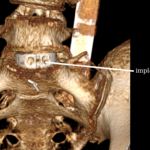

Implantacja implantu międzytrzonowego

- Duży cage ALIF (lordotyczny),

- Często:

- płytka przednia lub

- śruby kotwiczące w trzonach.

Stabilizacja dodatkowa (opcjonalna)

PSF (posterior spinal fixation):

- przy niestabilności,

- przy kręgozmyku,

- przy wielopoziomowych zmianach.